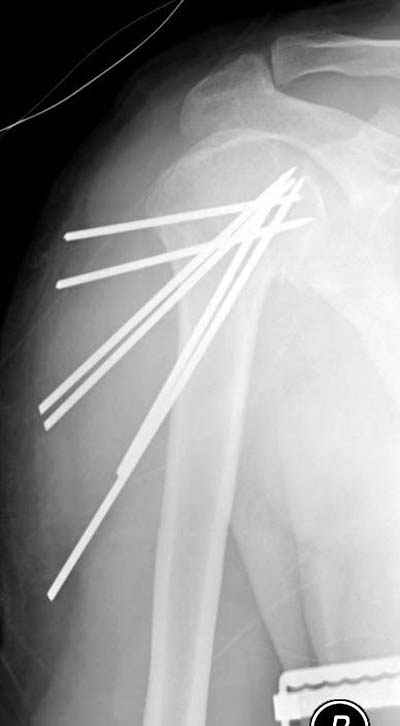

Здравствуйте, Евгений. В используемых Вами методиках остеосинтеза переломов хирургической шейки плечевой кости имеются ряд недостатков. Метод Лазарева хорош, как малоинвазивное вмешательство, но автор умалчивает о таких осложнениях как миграция спиц. Консолидация перелома начинается с резорбции костной ткани в месте перелома, в связи с этим спицы выходя за пределы субхондрального слоя головки плеча, и мигрируют в полость сустава, обеспечивая импиджмент синдром. Накостные фиксаторы (какие бы они не были) чаще используются для открытого остеосинтеза, что неизбежно ведёт к нарушению кровообращея в головке, далее к элементам асептического некроза с вытекающими последствиями. Обратите внимание на метод спирального остеосинтеза, который по философии отвечает принципам остеосинтеза при низкой минеральной плостности кости. Эту методику я внедрил 2 года назад, и она себя оправдывает. Статью по этому поводу Вы можете найте в сборнике съезда травматологов России, которых был в Саратове. (см фото) С Уважением, Комков Андрей.

Просмотрел приложенный снимок пенетрации спиц в сустав. Мне кажется, здесь были некоторые отклонения от рекомендованного доктором Лазаревым варианта. Метод называется "фиксация напряженными спицами", т.е после внедрения в головку концы спиц расходятся! А следующий фиксатор укрепляет позицию, удерживает от смещения! Поэтому, чем больше спиц, тем лучше создается жесткость и это предупреждает миграцию.

В Вашем случае получилась обычная фиксация спицами, т.е. спицы вошли в головку параллельно и не раздвинулись! В прошлом примеры идеальной установки напряженных спиц, кроме доктора Лазарева, показал Женя Чекашкин из Намибии.

Возможности фиксатора Лазарева я не идеализирую, и, возможно, другие коллеги также наблюдали случаи миграции, но от этого "феномена" никуда не уйти. Играет роль активность больного и качество кости. Приходилось видеть миграцию не только при малоинвазивных, а также в более устойчивых видах фиксации (пластин с угловой стабильностью).